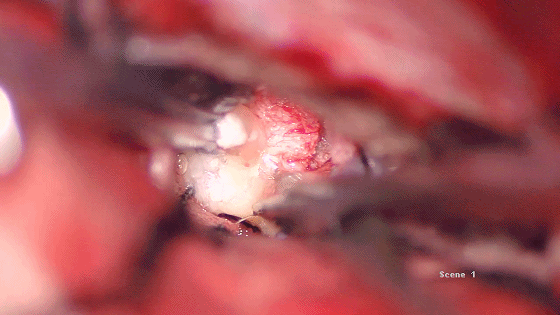

双侧基底静脉间发现肿瘤,部分钙化

瘤内分块切除减压

肿瘤部分质地软